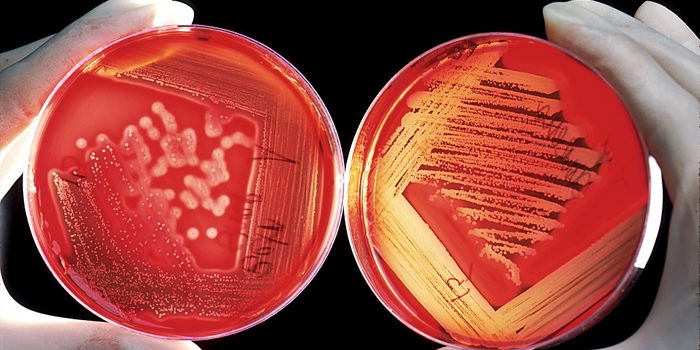

MAR 18, 2024MicrobiologyBy principle, quality control (QC) in the clinical laboratory must subject all instrumentation, assays, materials, and m ...